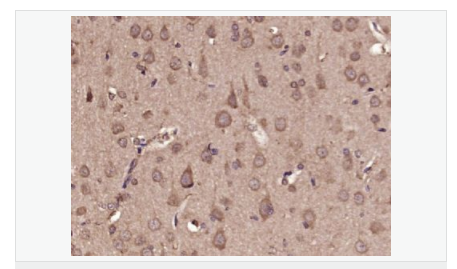

交叉反應(yīng):Rat,Mouse,Human(predicted:Sheep,Rabbit,Horse,Cow,Pig,Dog) 推薦應(yīng)用:IHC-P,IHC-F,IF,ELISA

| 產(chǎn)品應(yīng)用 | WB=1:500-2000 ELISA=1:5000-10000 IHC-P=1:100-500 IHC-F=1:100-500 ICC=1:100-500 IF=1:100-500 (石蠟切片需做抗原修復(fù)) not yet tested in other applications. optimal dilutions/concentrations should be determined by the end user. |